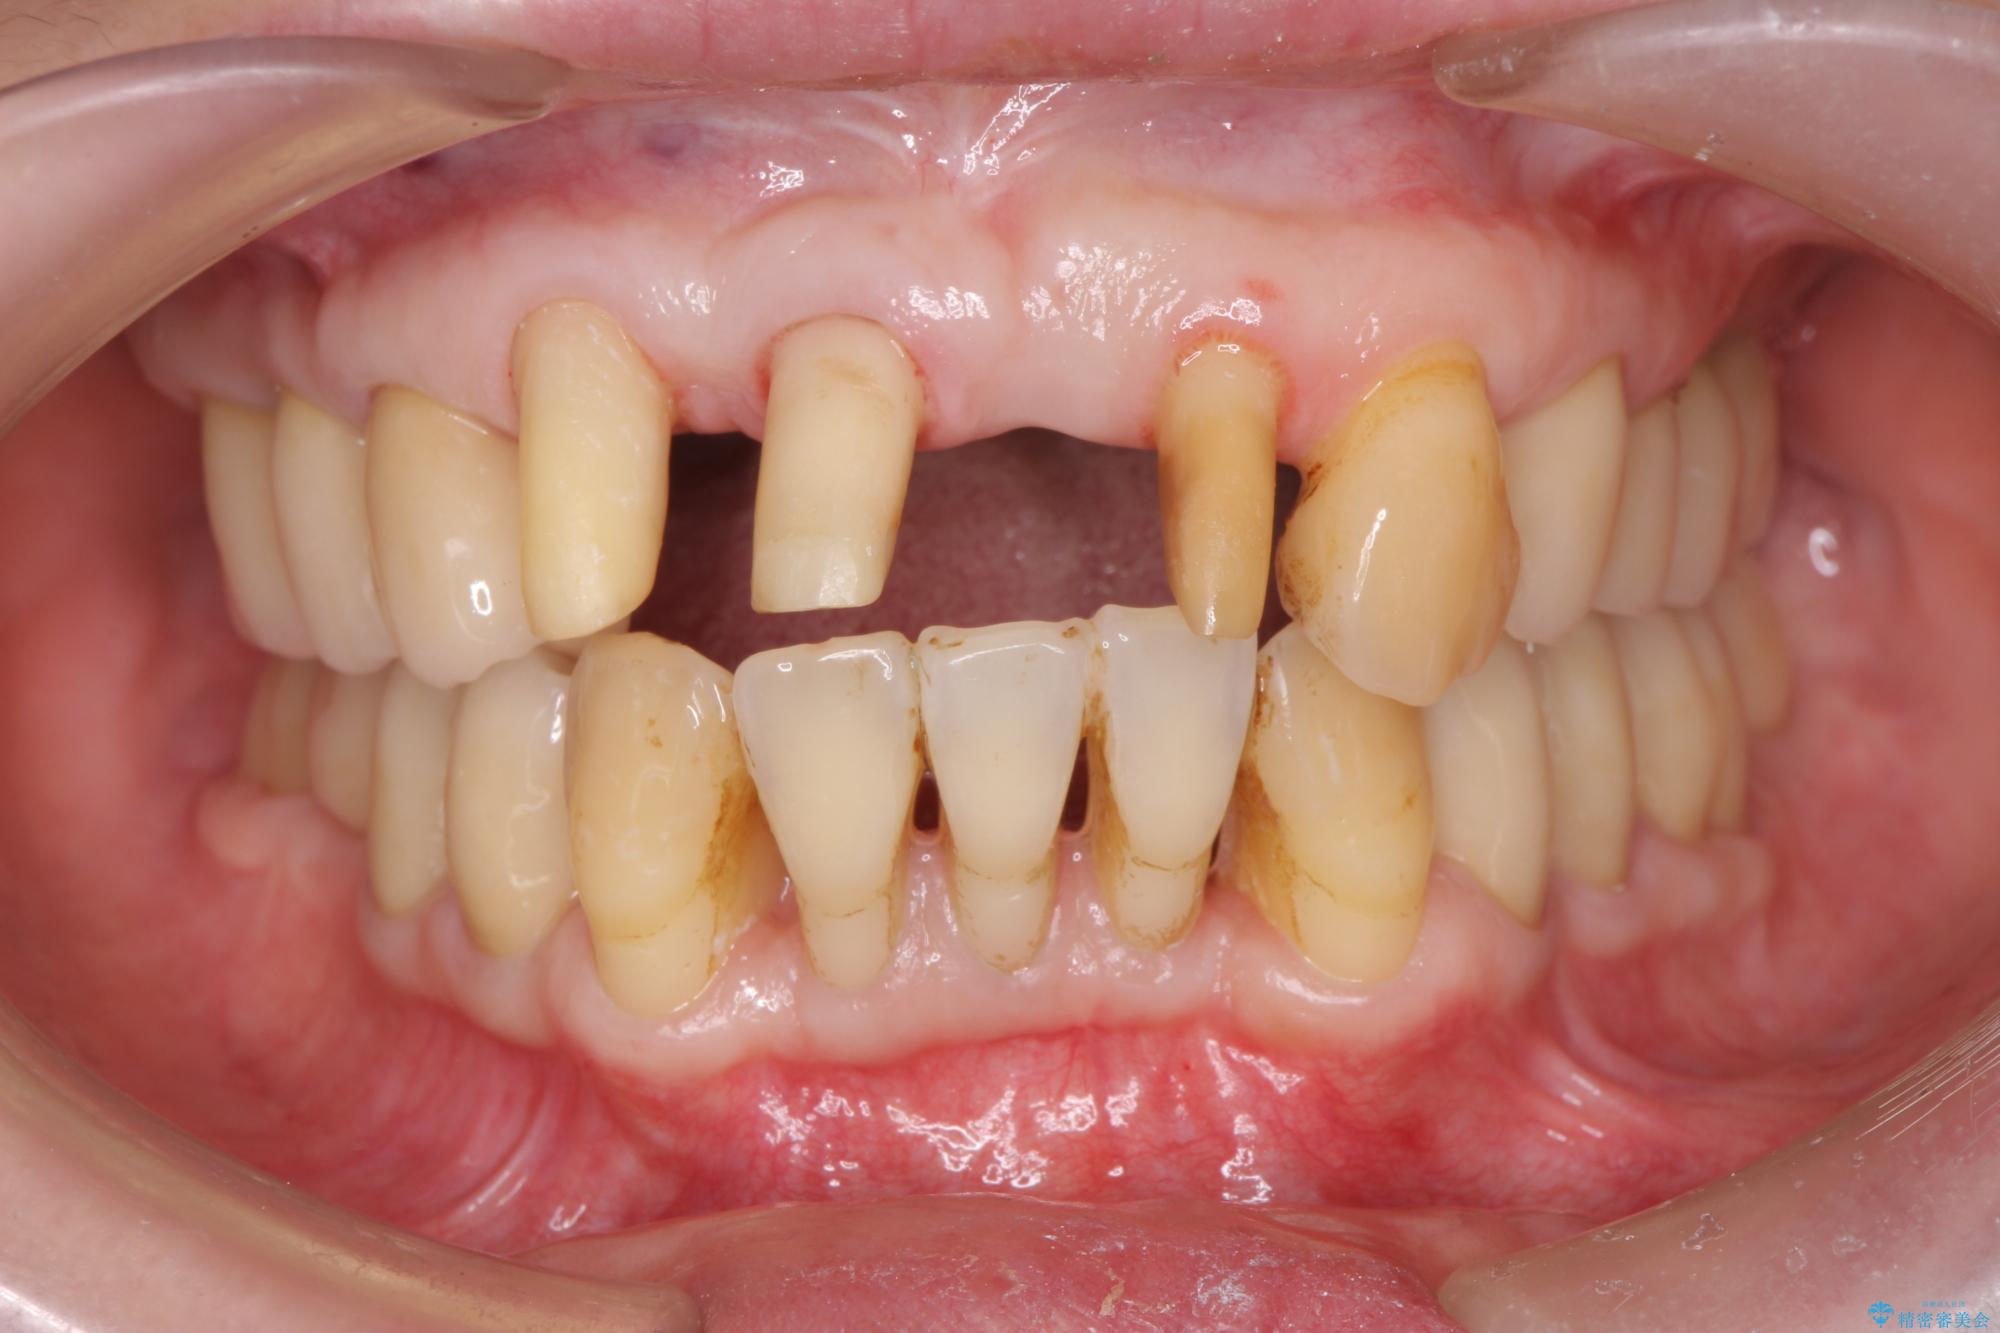

治療前

歯の総合的なマネージメントを行う包括的歯科治療の実践[ 歯周病・矯正・セラミック補綴 ] 治療前画像 歯の総合的なマネージメントを行う包括的歯科治療の実践[ 歯周病・矯正・セラミック補綴 ] 治療前画像 歯の総合的なマネージメントを行う包括的歯科治療の実践[ 歯周病・矯正・セラミック補綴 ] 治療前画像 歯の総合的なマネージメントを行う包括的歯科治療の実践[ 歯周病・矯正・セラミック補綴 ] 治療前画像 歯の総合的なマネージメントを行う包括的歯科治療の実践[ 歯周病・矯正・セラミック補綴 ] 治療前画像 歯の総合的なマネージメントを行う包括的歯科治療の実践[ 歯周病・矯正・セラミック補綴 ] 治療前画像 歯の総合的なマネージメントを行う包括的歯科治療の実践[ 歯周病・矯正・セラミック補綴 ] 治療前画像